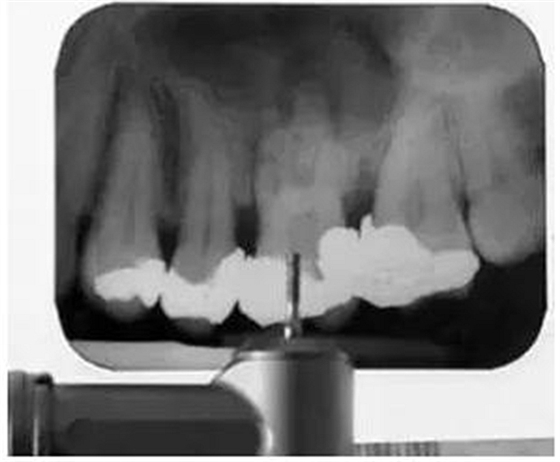

為了確保實現(xiàn)滿意的治療效果,在治療中要不斷確認工作長度和充填質(zhì)量。在備樁或者進行鈣化根管的根管治療時,要拍攝根尖X線片以確保鉆或根管銼的方向是正確的(圖4)。這可以有效地防止治療失誤,如不必要的髓室底或者側(cè)壁穿孔。